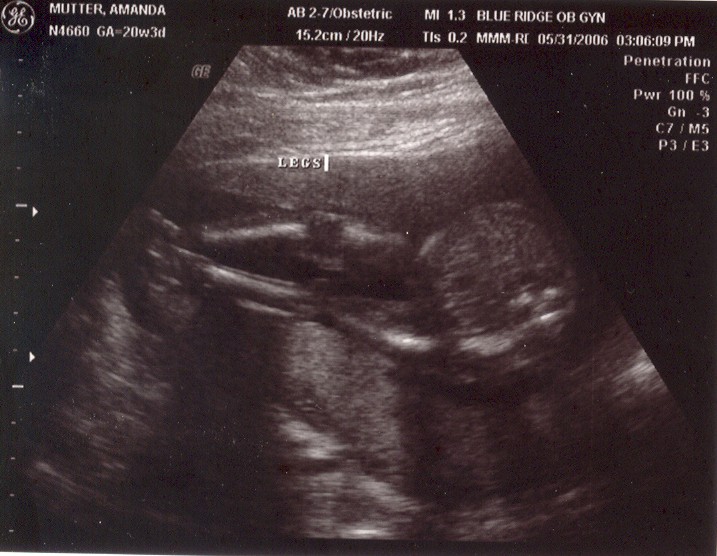

May 31, 2006: Diagnostic Ultrasound

OBs regularly do these to check if babies have all the right number of arms, brains, etc.